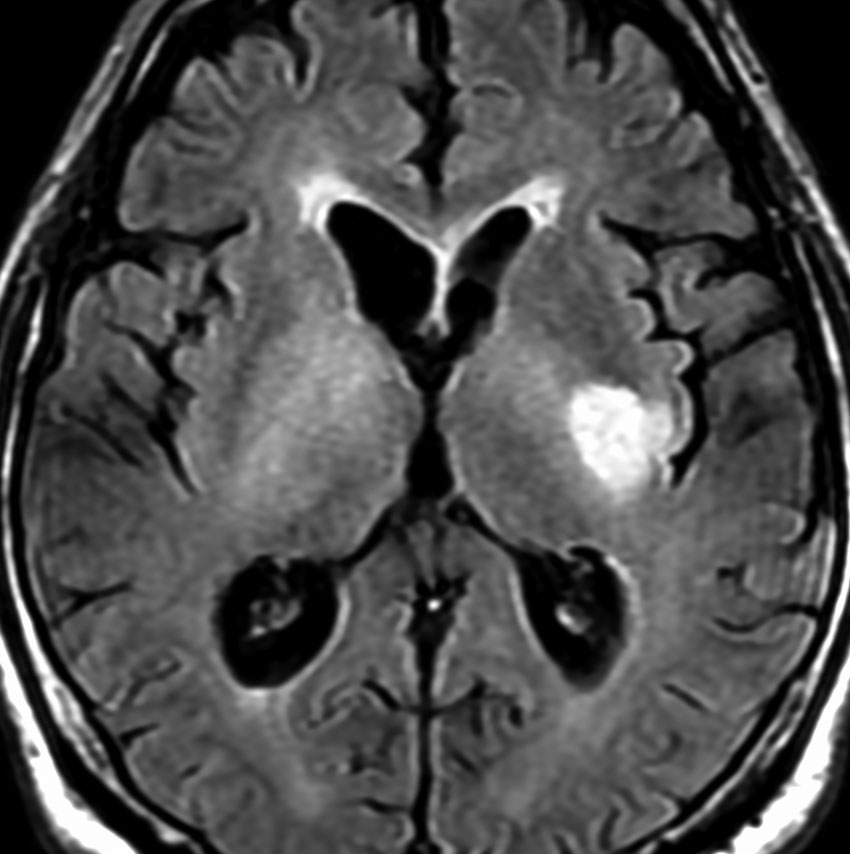

MRI画像所見 60代で嚥下障害と構音障害で発症した例

延髄から中脳まで腫瘍があって脳幹部が腫れています。この画像ですと,小児のびまん性橋膠腫(DIPG,びまん性正中グリオーマ)のように見えます

両側視床から大脳基底核,両側大脳半球深部白質,脳梁まで広範囲に腫瘍が存在します。退形成性星細胞腫のようにまだらにガドリニウム増強されます。